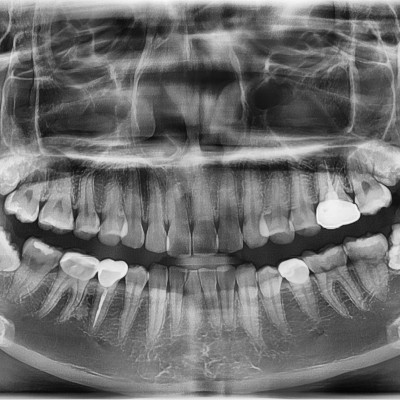

#18,28,38,48 사랑니 발치 #18,28,38,48 사랑니 발치 구강 외과 전문의가 당일 발치했습니다. --------------------..

작성자 이턱이 작성일 02-04 조회 1